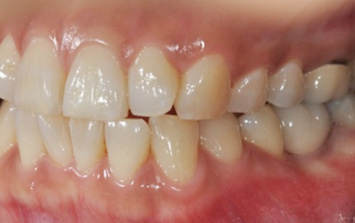

오른쪽 앞니 상실로 내원한 환자분. 앞니의 상실로 치아 사이 틈이 넓어지고 있어 교정으로 임플란트 식립 공간을 만든 후

임플란트 식립을 하였습니다. 앞니가 상실된 기간이 길어 교정치료를 하지 않고 임플란트를 식립할 경우

벌어진 치아 사이로 음식물이 끼거나 치아형태 이상으로 문제가 생길 수 있습니다.